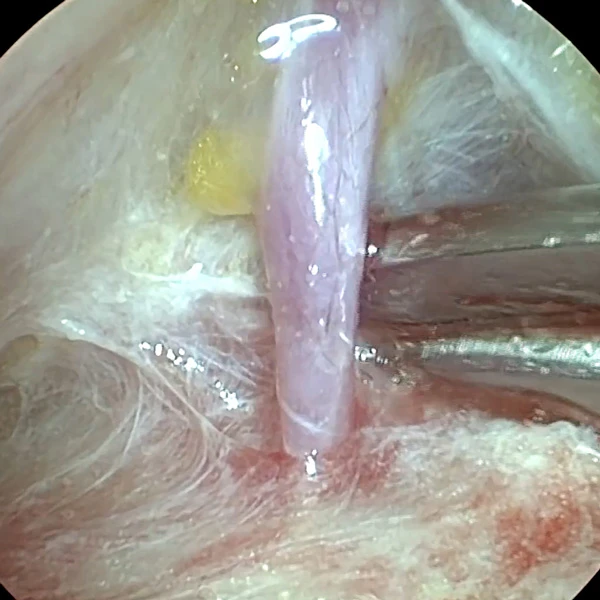

Второе пространство – межфасциальное. Оно находится между темпоропариетальной фасцией (Слой 3) и поверхностным листком собственной височной фасции (Слой 4) (Рис. 3). Это самый безопасный слой, который представлен рыхлыми волокнами соединительной ткани. Их называют «волосы ангела» (Рис. 4).

Височный лифтинг филлерами Neauvia

Рисунок 3

Рисунок 4